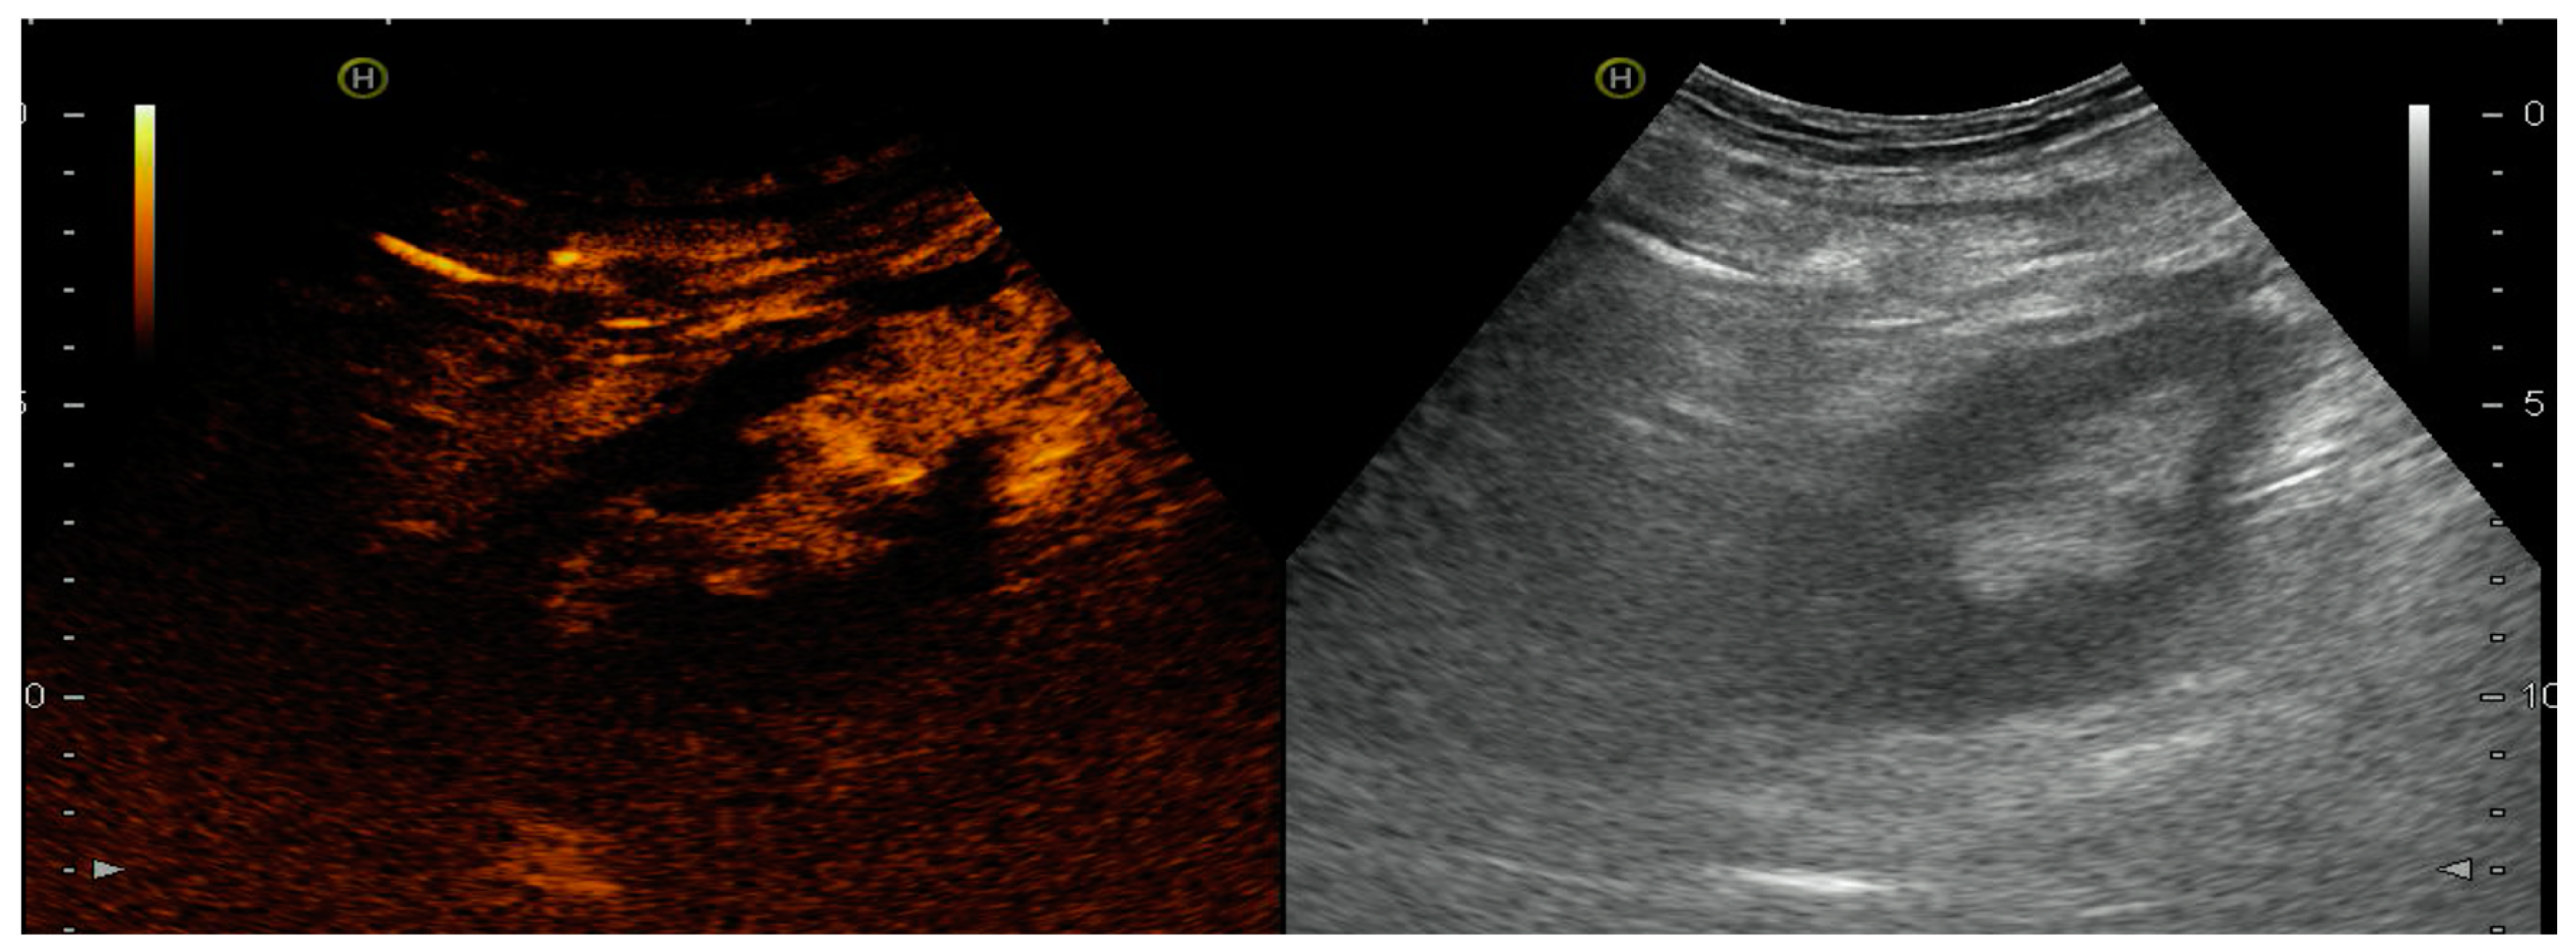

4.1.2. Venous Thrombosis